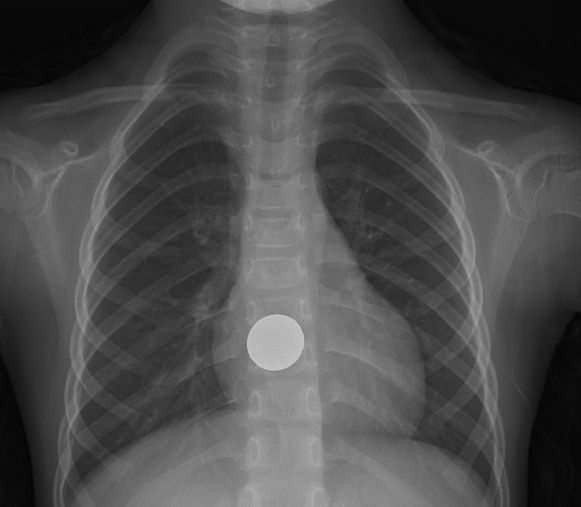

이물의 크기와 종류, 위장관 내 위치와 머문 시간에 따라 이물 제거 시기와 방법이 다르다. 먼저 X-ray 검사로 대략적인 이물의 위치나 크기, 모양을 확인할 수 있지만, 생선 뼈, 닭 뼈, 고기 등 음식물을 비롯해 유리, 알루미늄, 플라스틱, 나무로 만든 이물 등은 X-ray 검사에 잘 나타나지 않으므로 추가적인 내시경 검사가 진단 겸 치료에 도움이 된다.

동전 등 둔탁한 물질은 식도에 있더라도 24시간 이내에 제거하는 것을 권한다. 위에 위치한 이물이 날카롭거나 뾰족한 경우와 배터리가 48시간 이상 머물렀거나, 2개 이상의 자석은 금식 후 내시경으로 제거해야 한다.